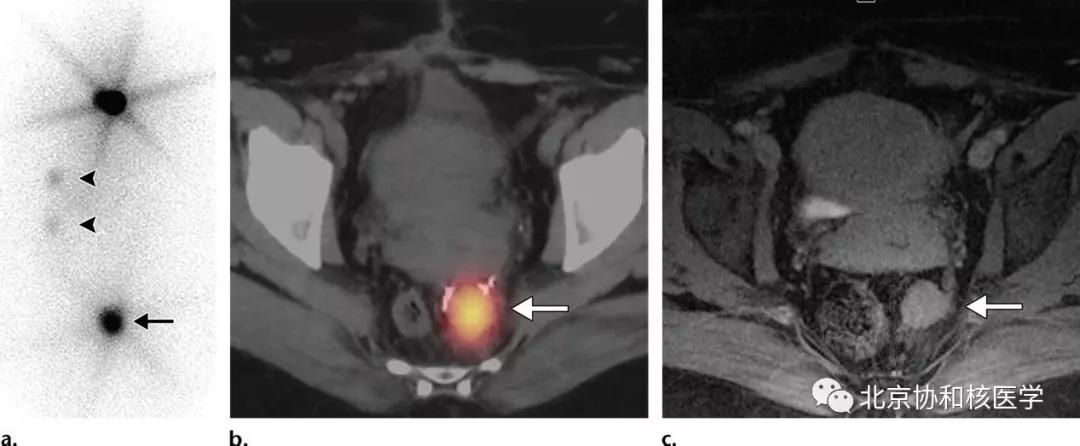

39岁女性,恶性卵巢甲状腺肿病史,行右侧卵巢切除术、甲状腺切除术、碘131治疗,碘扫可见残余甲状腺摄取、盆腔转移灶摄取及肝转移灶摄取:

36岁女性,乳头状甲状腺癌甲状腺全切除术后,碘131治疗后7天显像见子宫内膜区摄取,考虑为碘在经血中滞留所致:

38岁女性,甲状腺全切除术后(乳头状癌),碘131治疗后7天显像见乙状结肠局灶性摄取: